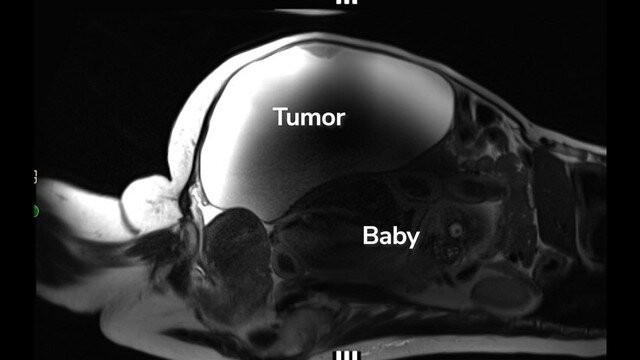

Điều bất ngờ chưa dừng lại ở đó, khi các bác sĩ tiếp tục kiểm tra sâu hơn và phát hiện cô không chỉ mang thai mà em bé đã phát triển đủ tháng, đặc biệt là nằm ngoài tử cung và bị “che giấu” hoàn toàn phía sau một khối u nang nặng gần 10kg.

Ngay lập tức, Lopez được chuyển đến Trung tâm Y tế Cedars-Sinai (Los Angeles) để thực hiện một ca phẫu thuật đặc biệt. Đội ngũ khoảng 30 bác sĩ và nhân viên y tế thuộc nhiều chuyên khoa đã phối hợp để vừa lấy thai, vừa loại bỏ khối u. Đây là một ca can thiệp cực kỳ phức tạp, bởi thai nhi phát triển ở vị trí bất thường, lại liên quan đến nhiều cơ quan trong ổ bụng.

Theo chia sẻ từ bác sĩ, chính việc thai nhi nằm phía sau khối u lớn đã đẩy các cơ quan khác sang vị trí khác, khiến Lopez không nhận ra những dấu hiệu mang thai. Bản thân cô cũng có chu kỳ kinh nguyệt không đều và thường xuyên cảm thấy khó chịu vùng bụng, nên càng khó phát hiện sự bất thường.